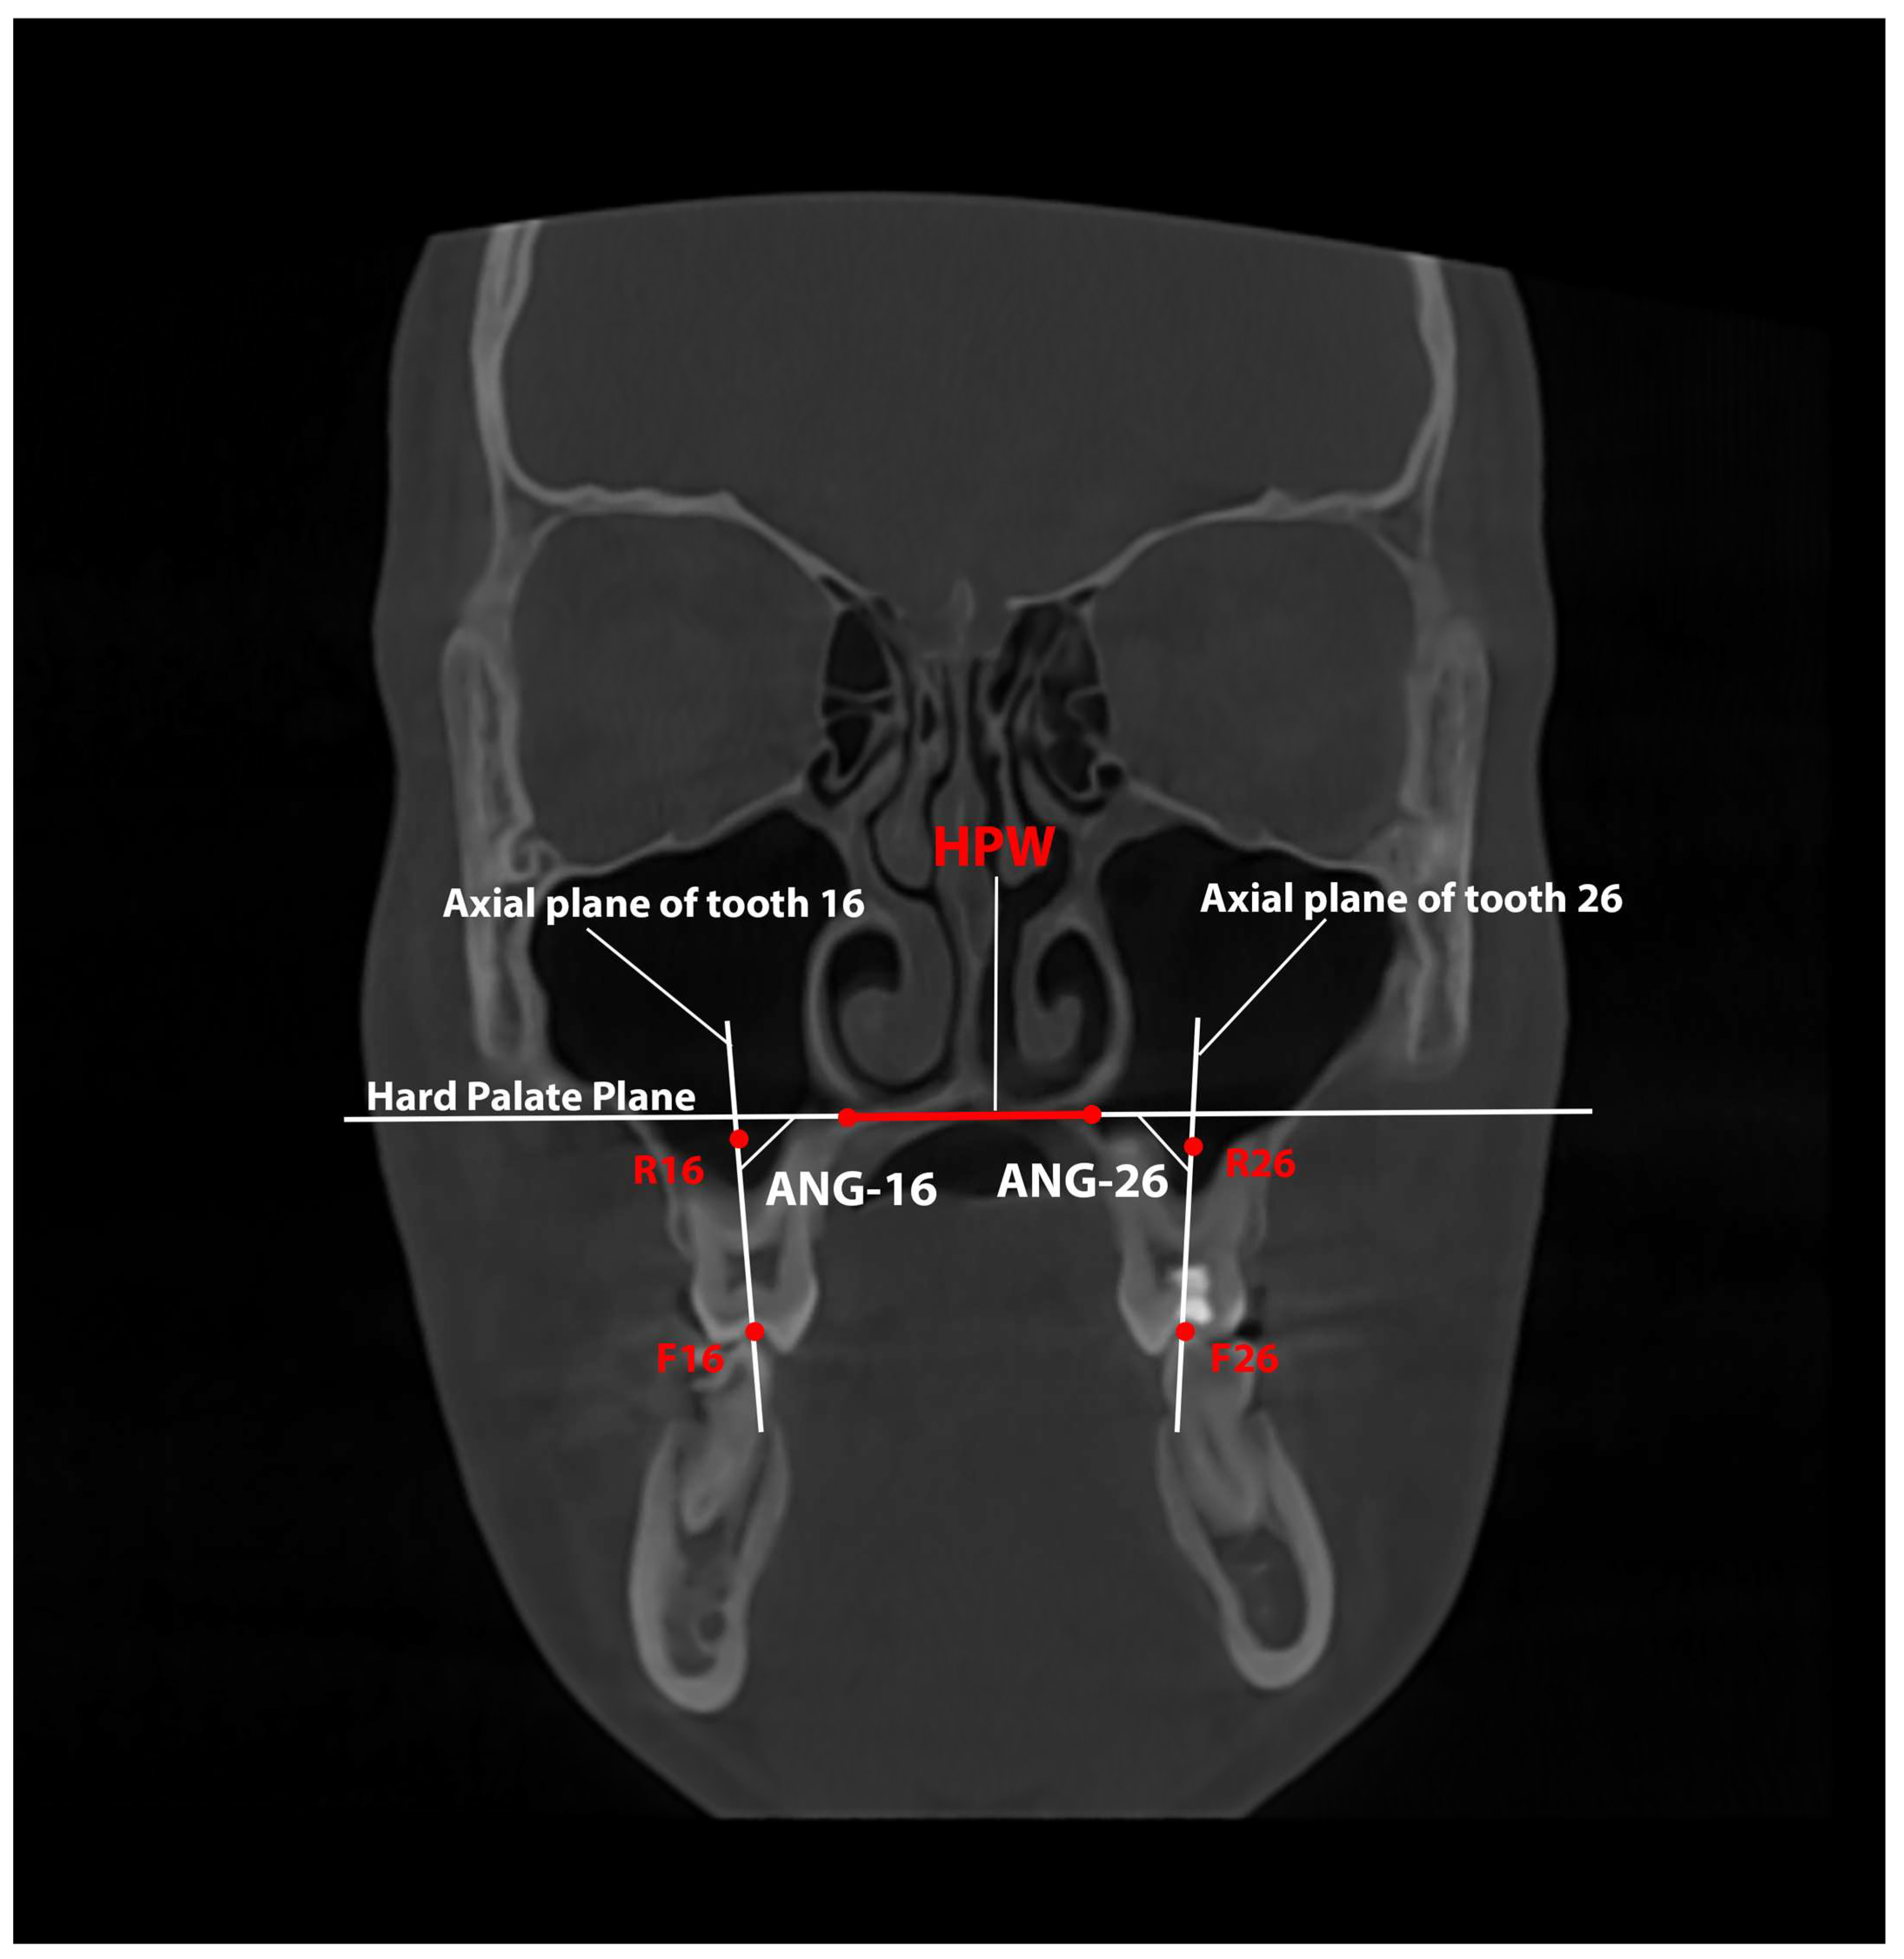

| Variable | Definition |

|---|---|

| ANG-16—Angulation of tooth 16 | The inner angle between the axial tooth plane (defined from F16, the midpoint of the central fossa, to R16, the midpoint between the roots) and the plane that defines the HPW. |

| ANG-26—Angulation of tooth 26 | The inner angle between the axial tooth plane (defined from F26, the midpoint of the central fossa, to R26, the midpoint between the roots) and the plane that defines the HPW. |